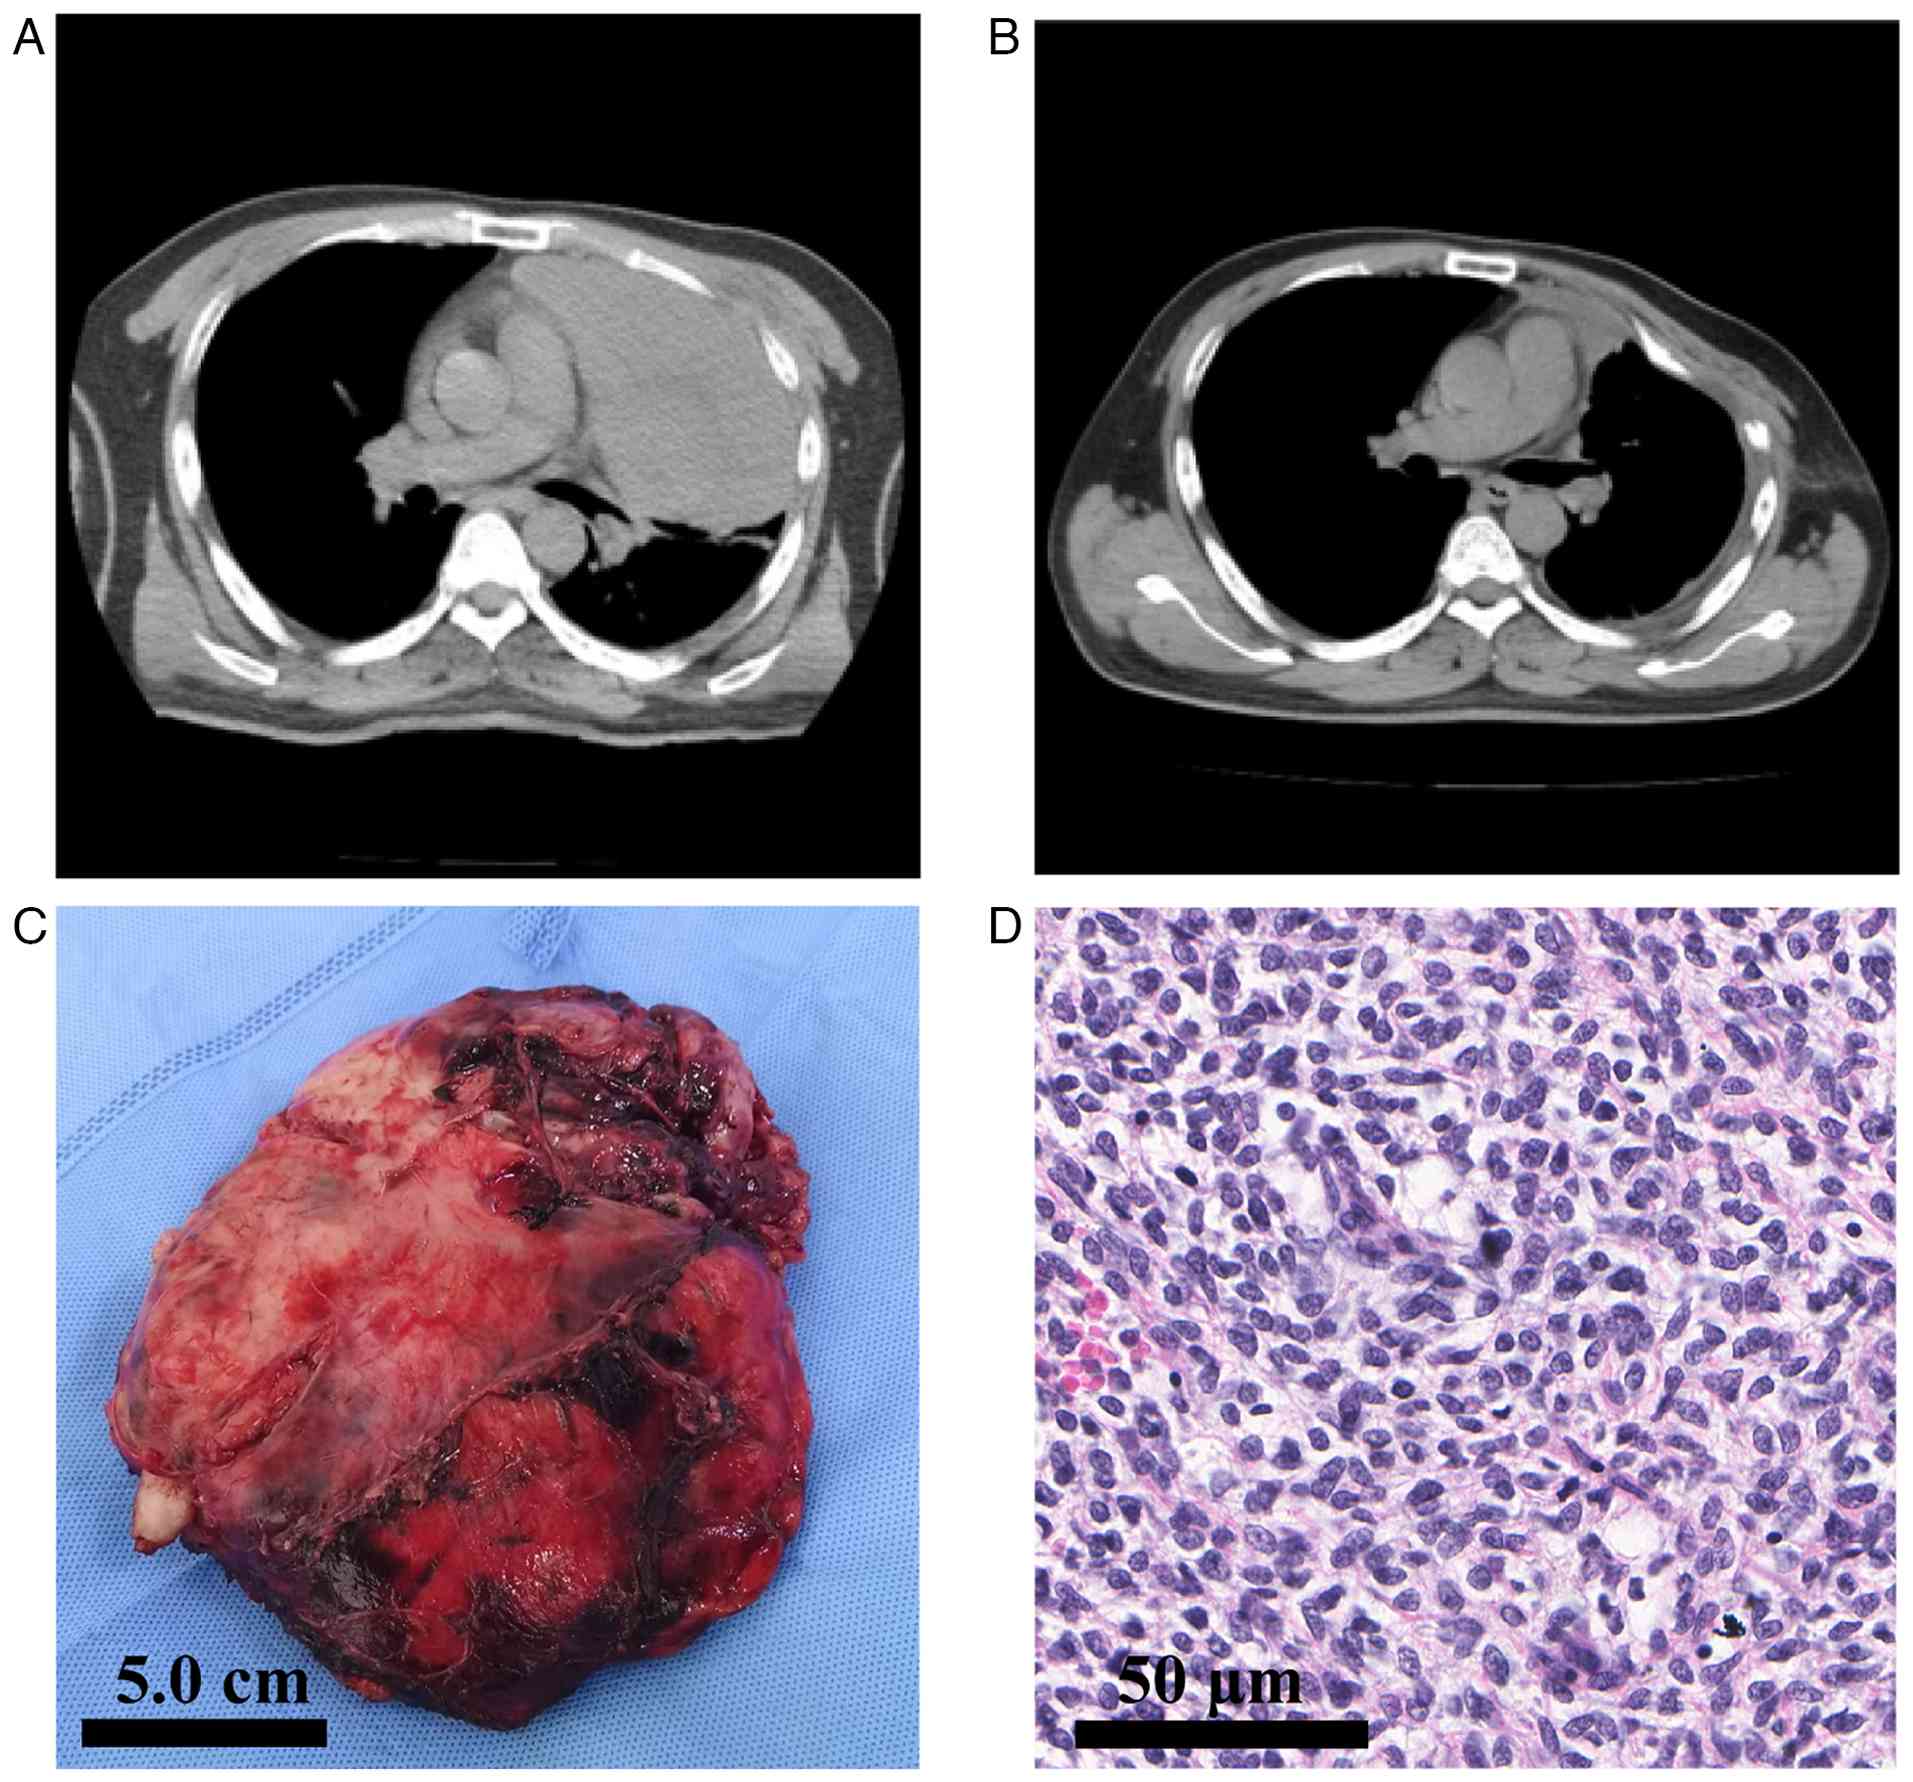

A 45-year-old male presented to The Second Forestry Hospital of Heilongjiang Province (Yichun, China) in April 2021 with persistent chest pain and dyspnea. The patient's medical history was notable for chronic smoking, with no other significant comorbidities. On initial examination, the patient appeared normal but exhibited mild respiratory distress (10). Chest X-ray revealed a large mass in the left hemithorax. Additional imaging with a computed tomography (CT) scan confirmed the presence of a tumor mass measuring 18.5×16.4×9.3 cm, localized to the left thoracic cavity, with broad contact to the parietal pleura but no clear chest wall invasion (Fig. 1A). The preoperative staging work-up included contrast-enhanced chest CT, non-contrast head CT and abdominal ultrasonography. Based on these examinations, no evidence of distant metastasis was detected. A positron emission tomography-CT scan, which could have provided a more comprehensive metastatic survey, was not performed due to the patient's financial constraints. All laboratory tests, including complete blood count; renal, liver and coagulation profiles; and tumor markers (cancer antigen 125, cancer antigen 153 and carcinoembryonic antigen), were within their normal ranges.

Radiological, gross and

histopathological findings of the primary thoracic synovial

sarcoma. (A) Axial contrast-enhanced chest CT scan (mediastinal

window) reveals a large, heterogeneous mass (18.5×16.4×9.3 cm)

occupying the anterior left hemithorax. The mass causes a

substantial mass effect, leading to compressive atelectasis of the

left lung. No definite mediastinal lymphadenopathy was identified.

(B) A follow-up chest CT scan (mediastinal window) on postoperative

day 5 shows successful re-expansion of the left lung, with no

residual pneumothorax or significant pleural effusion. (C) Gross

specimen of the resected tumor following left pneumonectomy. The

tumor measured 18.5 cm in diameter and appeared solid and tan in

color, with visible areas of hemorrhage. (D) Histopathological

examination (hematoxylin and eosin staining; original

magnification, ×400; scale bar, 50 µm) demonstrates hypercellular

proliferation of uniform spindle-shaped cells with indistinct

cytoplasm arranged in intersecting fascicles, consistent with the

monophasic variant of synovial sarcoma.

Figure 1.

Radiological, gross and histopathological findings of the primary thoracic synovial sarcoma. (A) Axial contrast-enhanced chest CT scan (mediastinal window) reveals a large, heterogeneous mass (18.5×16.4×9.3 cm) occupying the anterior left hemithorax. The mass causes a substantial mass effect, leading to compressive atelectasis of the left lung. No definite mediastinal lymphadenopathy was identified. (B) A follow-up chest CT scan (mediastinal window) on postoperative day 5 shows successful re-expansion of the left lung, with no residual pneumothorax or significant pleural effusion. (C) Gross specimen of the resected tumor following left pneumonectomy. The tumor measured 18.5 cm in diameter and appeared solid and tan in color, with visible areas of hemorrhage. (D) Histopathological examination (hematoxylin and eosin staining; original magnification, ×400; scale bar, 50 µm) demonstrates hypercellular proliferation of uniform spindle-shaped cells with indistinct cytoplasm arranged in intersecting fascicles, consistent with the monophasic variant of synovial sarcoma.

Gross examination of the resected specimen (Fig. 1C) revealed a well-circumscribed, but unencapsulated, greyish-white soft tissue mass measuring 18.5×16.4×9.3 cm in the greatest dimension. The cut surface was solid and tan-white, with focal hemorrhagic areas and ~20% necrosis. Histological examination (Fig. 1D) demonstrated a hypercellular tumor composed of relatively uniform, spindle-shaped cells arranged in intersecting fascicles. The tumor cells exhibited oval nuclei, scant cytoplasm and predominantly monophasic fibrous morphology. Mitotic activity, assessed on H&E-stained sections, was elevated, with an average of 12 mitoses per 10 high-power fields. An extensive IHC panel was performed as described above, using ready-to-use primary antibodies (prediluted 1:100; Fuzhou Maixin Biotechnology Development Co., Ltd.), which revealed diffuse nuclear positivity for transducin-like enhancer of split 1 (TLE1; cat. no. MAB-0686) (Fig. 2C) and membranous positivity for CD117 (c-kit; cat. no. Kit-0029) as well as focal immunoreactivity for epithelial membrane antigen (EMA; cat. no. MAB-1101) and low-molecular-weight cytokeratins [CK (cat. no. RAB-0050) and CK19 (cat. no. MAB-0829)] (Fig. 3A-D). The tumor was entirely negative for STAT6 (nuclear; cat. no. RMA-1066) (Fig. 2D), which effectively ruled out the diagnosis of SFT. A mesothelial marker panel [Calretinin (cat. no. MAB-0716), Wilms tumor-1 (cat. no. RMA-1151), D2-40 (cat. no. MAB-0567) and CK5/6 (cat. no. RMA-1144)] also yielded a negative result, excluding the diagnosis of sarcomatoid mesothelioma (Fig. 4A-D). The Ki-67 (cat. no. RMA-0542) proliferative index was ~30%, indicating a moderately high rate of cell proliferation (Fig. 2E) (13,14). The surgical margins were positive for tumor cells (R1 resection), with the closest margin measuring <1 mm at the mediastinal aspect. The diagnosis was confirmed cytogenetically by fluorescence in situ hybridization (FISH) using the Vysis SS18 Break Apart FISH Probe Kit (Abbott Molecular), performed strictly according to the manufacturer's protocols. The analysis revealed a rearrangement of the SS18 (SYT) gene locus in 80% of the nuclei assessed, and thus, fusion-specific SS18-SSX IHC was not performed (Fig. 2F). Pathological staging of the tumor was T4G3NxM0, which is classified as stage III according to the American Joint Committee on Cancer staging system (15,16).